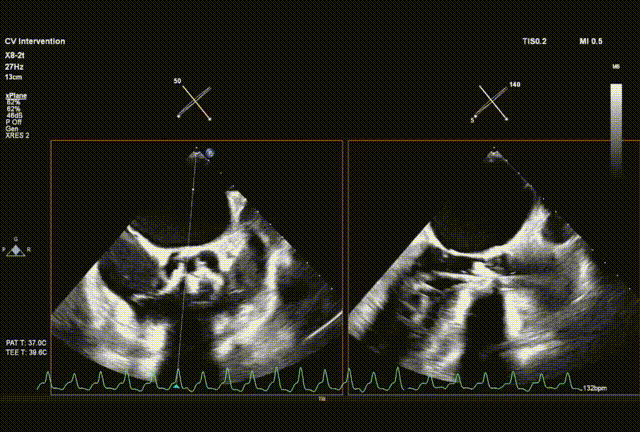

左右旋转系统并前送,观察无瓣膜移动,回撤导丝后再撤出系统

术后超声评估,未见瓣周漏,平均跨瓣压15 mmHg,血流速度197 cm/s